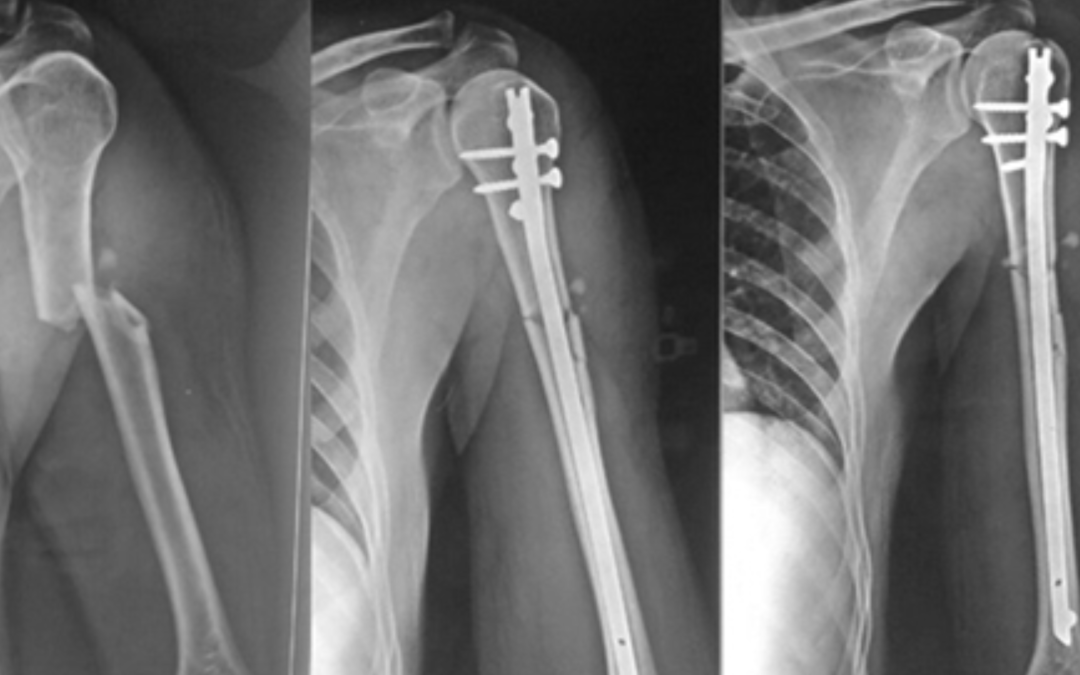

Understanding Interlocking Nail Systems: A Guide to Modern Intramedullary Fixation

by ao@ca | Mar 7, 2026 | Post

The field of orthopedic surgery has undergone a massive transformation over the last few decades. Among the most significant advancements in trauma care is the evolution of internal fixation techniques for long bone fractures. When a person suffers a severe break in...